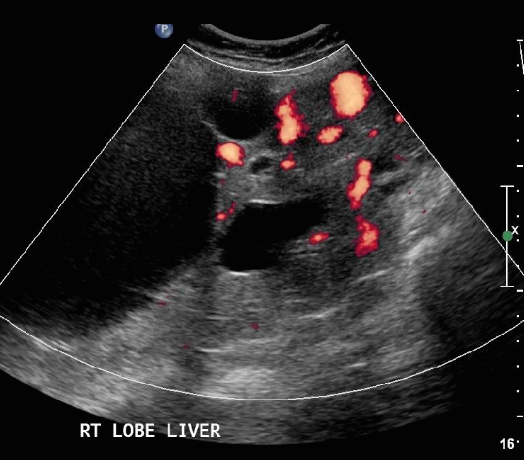

⑤ cavernous hemangioma(혈관종)

정맥의 혈액으로 채워진 여러 개의 작은 혈관에 혈류의 흐름이 느려져 혈전이 형성된 후 종괴처럼 보이는 것을 혈관종이라고 한다. 간의 양성종양 중 가장 흔한 질환이다. 초음파상 우연히 발견되며 거의 증상이 없다. 여성에서 5배 더 흔하고 분만경험이 있는 30-40대 여성에 많이 발견된다. 대부분 단발성으로 우측 간의 피막하나 혈관주위에 발생한다.

US finding

- 2cm 이하는 내부 균일한 고에코 종괴로 보인다

- 3cm 정도 되면 내부에코가 약간 저하된 종괴로 보인다

- 5cm 이상은 고에코와 저에코가 뒤섞인 복합성 에코종괴로 보인다

- color doppler 검사 시 내부 혈액의 흐름이 없다

- 환자의 자세를 바꾸면 에코가 저하된다(chameleon sign )

- 프로브로 압박하면 에코가 달라진다 (disappering sign)

- 시간이 경과함에 따라 내부에코의 변화(wax and wane sign)